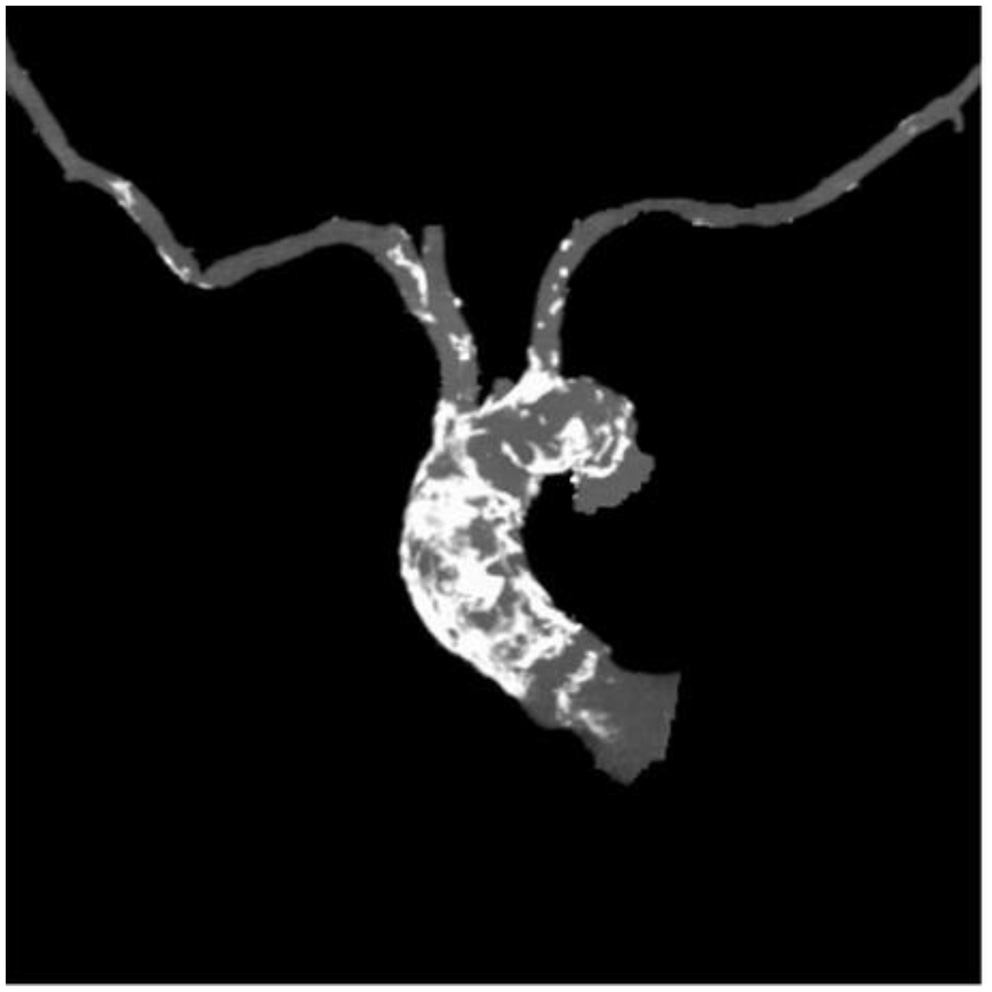

Table 1 outlines all baseline characteristics for the 56 patients. The patients were 29 (51.7%) male and 27 (48.3%) female, who were 74±15 years old (range 62 −89). The mean logistic EuroSCORE was 10.17%, the mean Society of Thoracic Surgeons score was 3.22%. One third of the patients were categorized as class III or IV of the New York Heart Association (NYHA). Almost half of the patients had concomitant coronary artery disease (48.2%). Myocardial revascularization was previously performed in 46.3% (PCI in 16%, CABG in 30.3%). 7.1% of patients had carotid disease, while 14.2% of patients had lower extremity artery disease. As such, 12% of patients needed to undergo a surgical cut as a vascular approach due to the nature of the disease (mainly heavy classifications). One patient also had severe stenosis of the popliteal artery. Lung disease was found in 25%, chronic kidney disease was present in 14.2% patients (i.e., one patient was on hemodialysis). The presence of porcelain aorta was considered to be direct indication for a TAVI in 14.2% of patients (Figure 2). TAVI was suggested to 2 patients due to chest deformation and previous chest irradiation. The mean left ventricle ejection fraction was 44% (range 15–65%), while the mean of the aortic pressure gradient was 45 mmHg (range 29–106 mmHg). The average aortic valve area was 0.58 cm2 (range 0.4–0.9 cm2).

Figure 2

Porcelain aorta.